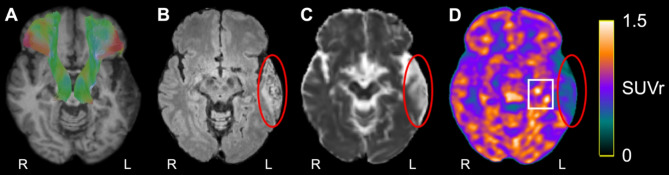

Results: [18F]FEPPA-PET, DTI, and T2-weighted FLAIR were acquired at 6-months post-stroke in 19 elderly humans (seven females; mean age = 76 ± 5 years) with confirmed first-ever acute ischemic stroke using hybrid PET/3T-MRI. Index infarcts, chronic (incidental, covert) infarcts, and WM hyperintensities were manually segmented on FLAIR and excluded from the imaging analysis. Pearson correlation was conducted to assess the association between [18F]FEPPA-SUVr and DTI measurements in WM regions commonly implicated in PSCI. [18F]FEPPA-SUVr was elevated in brain regions ipsilateral to the index infarct at 6-months post-stroke, and these increases correlated with decreases in fractional anisotropy in several WM pathways linked to PSCI, including right superior longitudinal fasciculus (SLF) III (r = -0.82, p < 0.0001), right anterior thalamic radiation (r = -0.61, p = 0.006), and right arcuate fasciculus (r = -0.56, p = 0.01). Elevated [18F]FEPPA-SUVr was also associated with increased mean diffusivity (r = 0.69, p < 0.001), axial diffusivity (r = 0.55, p = 0.02), and radial diffusivity (r = 0.74, p < 0.001) in right SLF III.

Conclusions: This study found an association between elevated post-acute glial activation (neuroinflammation) and reduced microstructure integrity in brain WM pathways ipsilateral to ischemic infarcts and remote from WM lesions at 6-months post-stroke. Hybrid PET/MRI is promising to be a valuable tool for probing post-acute neuroinflammation and associated changes in cerebral WM pathways following ischemic stroke.